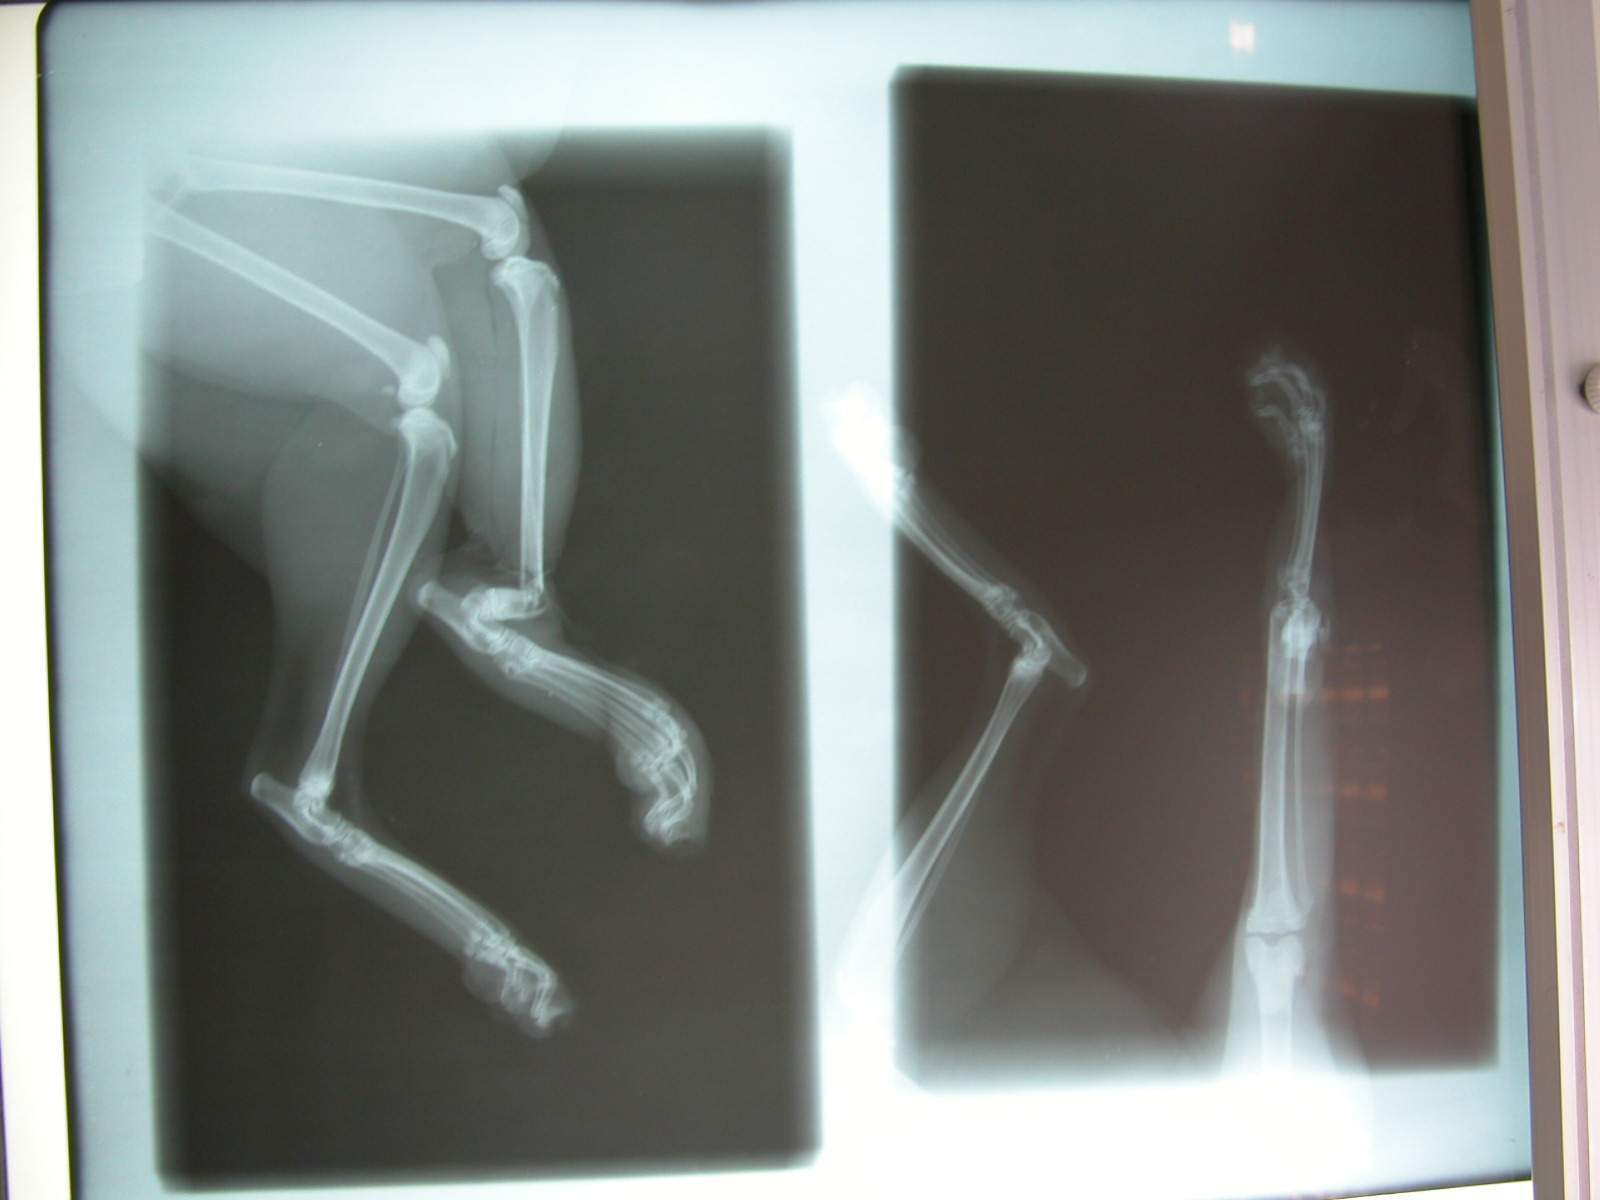

主題: 2/22凌晨捕獸夾貓咪 申請者姓名: 敏大哥 花色: 申請日期: 2012-02-25 16:49:54 申請者部落格: 申請者臉書網址: 所在縣市/合作醫院: 台北市/龍貓動物醫院 治療費用: 12100元 需求人數: 14人 已結案 (2012-05-29 19:58:36) 報名人員: 范立縈(已付款)、林麗香(已付款)、Kelly Ko(已付款)、Janice(已付款)、Kelly Ko(已付款)、Celene Chu(已付款)、莎拉拉(已付款)、Keke Chien(已付款)、張紋慈(已付款)、Mark Hsu(已付款)、黑嚕嚕(已付款)、Amber Tsai(已付款)、cleo(已付款)、Roger Hsu(已付款)、 候補人員: BJ(已付款)、貞子、Miki、 動物病情說明: 2/22凌晨由志工捕獲遭捕獸夾夾斷後肢的貓咪,經手術清創並接回斷骨,目前恢復狀況良好,後腳有很大機會可以保住,醫助款包含手術費用,X光片,住院醫療,二合一檢驗,除蚤